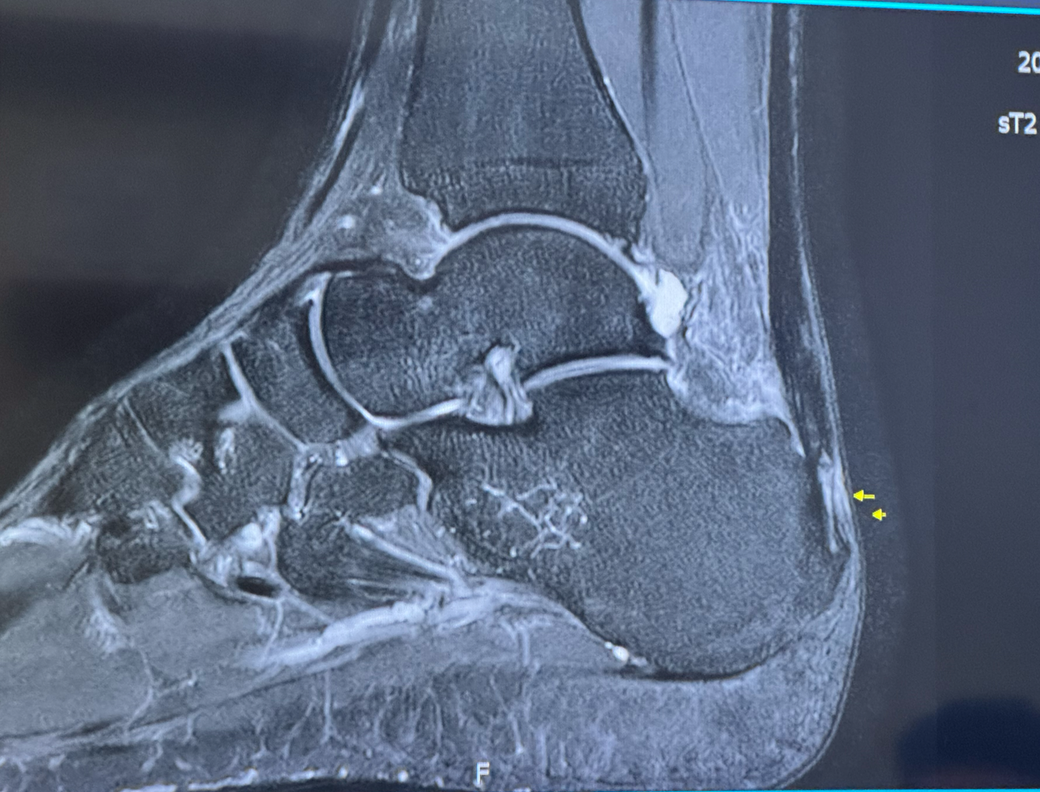

아킬레스 부착부에 일부 파열 및 하글런드 있다는 소견을 들었는데요

• 1번 째 사진